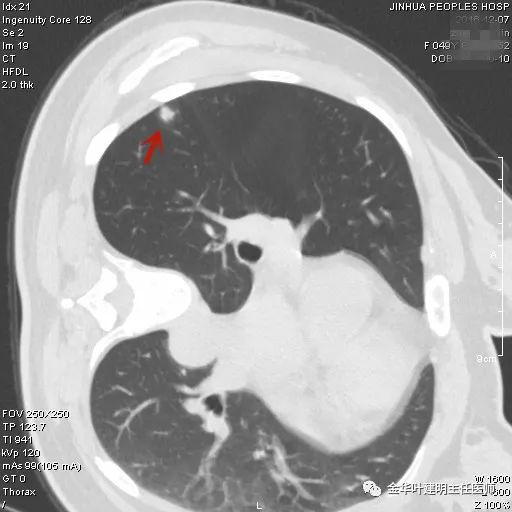

上图示硬化性血管瘤:此结节考虑良性可能性大,但要定具体性质仍是困难的,其密度均匀,边缘非常光滑,没有卫星病灶,没有渗出改变,收缩力不明显(邻近胸膜无牵拉)。